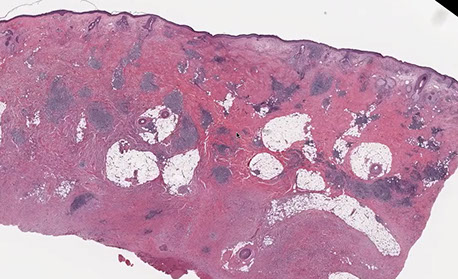

Eccrine poroma

Friable papule/plaque MC on sole/scalp surrounded by indented moat (demarcation); resembles pyogenic granuloma clinically

- or is it found on extremities of middle aged adults??

Micro: monotonous cuboidal/basaloid "poroid" tumor cells in lower part of acanthotic dermis has a broad base that extends into dermis

- sharp demarcation (moat) between normal skin and tumor

- tumor cells may have cytoplasmic clearing due to glycogen accumulation; can also have melanin

- can see small sweat ducts in tumor (vs seb k)

Variations: 1) Hydroacanthoma simplex, 2) Syringofibroadenomatosis, 3) Sebocrine adenoma

1) Basaloid/clear cell clone prolif. w/ lumen of ducts entirely w/in epidermis (like Borst_Jadassohn intraepidermal epithelioma

2) Uncommon, reticular prolif of ducts in dermis that connects to surface ( like fibroepithelioma w/ sweat ducts); may be from Schoepf syndrome

3) Sebaceous + apocrine diff in poroma-ish lesion

IHC: EMA (highlights luminal component of the ducts)